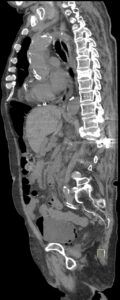

Figurile 1 şi 2: axial examinare CT abdomen şi pelvis fără substanță de contrast

Discuţie caz nr 131: pacient de 85 de ani cunoscut diabetic este adus la camera de gardă pentru dureri abdominale difuze, efectueaza CT fără substanță de contrast deoarece eGFR este 21 mL/min/1.73 m². Se evidențiază pericardita în cantitate medie, mai multe chiste renale – unul spontan hiperdens, multiple plăci aterotrombotice calcificate la nivelul aortei și ramurilor precum și multiple bule aerice în peretele vezicii urinare și conținut hidro-aeric al vezicii urinare. Ultimele două elemente sugerează diagnosticul de cistita emfizematoasă.